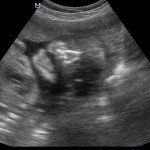

L’ecografia è una tecnica che consente di vedere gli organi del nostro corpo con l’utilizzo di onde sonore ad alta frequenza (ultrasuoni, non udibili dall’orecchio umano) che attraversano i tessuti. La sonda ecografica invia impulsi di onde sonore nel corpo. Quando le onde sonore arrivano al feto mandano degli echi: tali echi (o onde di ritorno) sono trasformati in immagini sul monitor dell’ecografo. Con l’ecografia è quindi possibile osservare in modo dettagliato il feto.

Le ragioni più comuni per cui si esegue una ecografia in gravidanza sono: determinare il numero degli embrioni o dei feti, visualizzare l’attività cardiaca fetale, determinare l’epoca di gravidanza, valutare l’anatomia e la crescita fetale, determinare la posizione del feto e della placenta

Nei primi mesi di gravidanza, con la misura della lunghezza del feto, è possibile valutare se lo sviluppo corrisponde all’epoca di gravidanza valutata in base alla data dell’ultima mestruazione, il numero dei feti e la presenza dell’attività cardiaca.

Dal secondo trimestre si misurano altre parti fetali, ed i valori di tali misure vengono confrontati con quelli delle curve di riferimento. Si può così valutare la normalità o meno della crescita fetale. Inoltre periodo si visualizzano la sede di inserzione placentare e la quantità di liquido amniotico.

- E’ possibile rilevare con l’ecografia anomalie fetali maggiori?

La possibilità di rilevare un’anomalia maggiore dipende dalla sua entità, dalla posizione del feto in utero, dalla quantità di liquido amniotico e dallo spessore della parete addominale materna; perciò è possibile che talune anomalie fetali possano non essere rilevate all’esame ecografico. Inoltre alcune malformazioni si manifestano tardivamente (al 7°- 9° mese) e perciò non sono visualizzabili in esami precoci. L’esperienza finora acquisita suggerisce che un esame ecografico routinario, non mirato, consente di identificare dal 30 al 70% delle malformazioni maggiori. Non è compito dell’ecografia la rilevazione delle cosiddette anomalie minori (Linee Guida SIEOG 2006).

A fianco alla più tradizionale ecografia eseguita per via transaddominale, risulta particolarmente utile nell’esame ecografico ostetrico e ginecologico la via di accesso transvaginale.

Con questa metodica, utilizzando delle sonde ecografiche appositamente predisposte (per forma e dimensione, e per frequenza di emissione degli ultrasuoni) è possibile controllare la gravidanza nel primo trimestre con una qualità e definizione d’ immagine nettamente superiori a quanto possibile per via transaddominale.

Con l’ecografia transvaginale è possibile vedere dopo circa 3 settimane dal concepimento la camera gestazionale nella cavità uterina. Successivamente è possibile visualizzare l’embrione (3-5 mm.) a circa 6 settimane dall’ultima mestruazione (4 settimane dal concepimento) ed a questo periodo è già visibile l’attività cardiaca fetale Anche i primi dettagli sulla morfologia fetale (polo cefalico, abbozzi degli arti) sono visualizzabili più precocemente con l’ecografia transvaginale, risultando essi visibili intorno a 8-9 settimane.

Con l’ecografia dei primi mesi di gravidanza, si può anche valutare la normalità dell’utero (eventuale presenza di fibromi già preesistenti alla gravidanza) e delle ovaie.